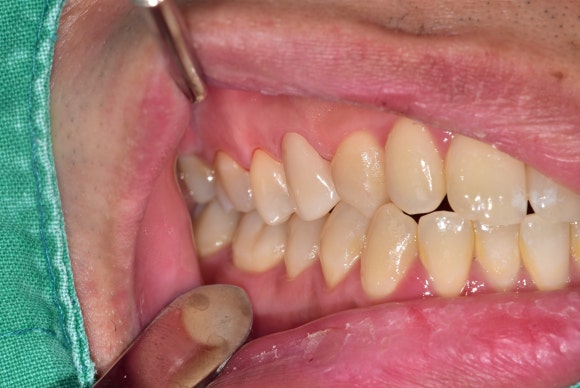

오늘 소개드릴 환자분은 20대의 건장한 남자분이십니다.

충치가 심해서 이가 한 번 깨진 적이 있었으나

시간 상 치료를 오랫동안 미뤄오셨습니다.